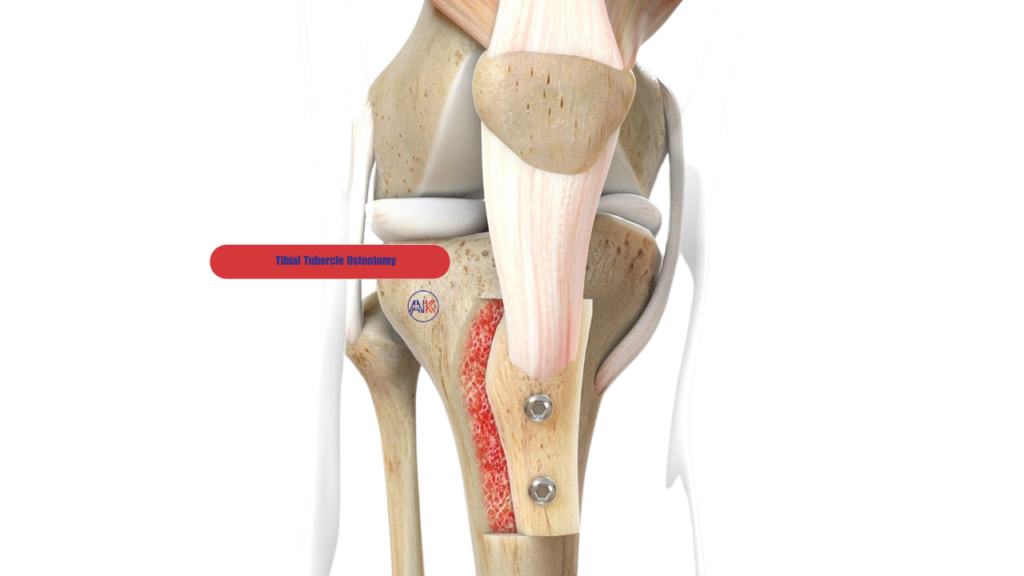

Tibial Tubercle Osteotomy

This procedure involves repositioning the tibial tubercle, the bony prominence on your shinbone where the patellar tendon attaches. Adjusting this attachment point can improve the alignment of your kneecap, reducing the risk of future dislocations and enhancing knee function.